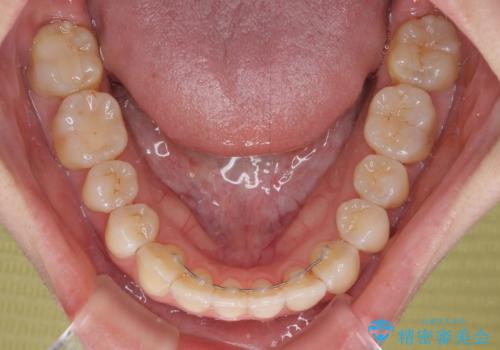

前歯にデコボコがあり、口元がやや突出した印象があったため、IPR(歯と歯の間を削る)と親知らずを抜歯した上での歯列全体の後方移動をメインに、インビザラインを用いて矯正治療を行うこととしました。

年に一度、夏休みの時期にしか帰国できないため、帰国のタイミングに合わせてマウスピース交換スケジュール治療計画としたため、3年半という期間を要しました。

留学先でもしっかりとマウスピースの装着を実践してくださったので、ご本人の満足のいく仕上がりとなりました。